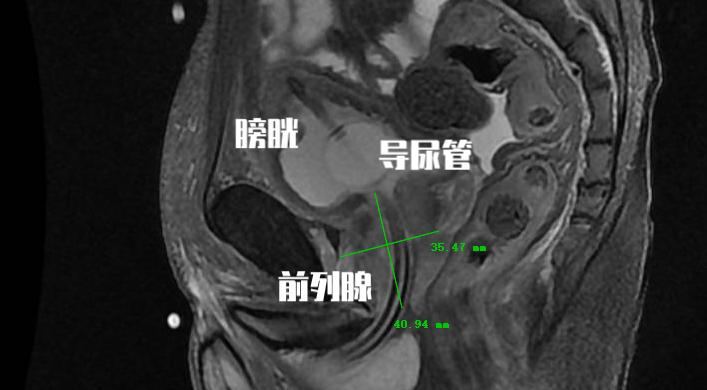

可能讲起来比较难以理解, 我们男性的排尿是当膀胱内充满尿液后会有排尿的冲动信号由膀胱传递至大脑,然后大脑在可以排尿的情况下将信号在传递至膀胱和尿道。这个时候膀胱开始收缩,尿道打开,小便就可以自然排出。而前列腺增生后会带来几种情况,它会刺激我们的膀胱,即使在尿量不充盈的时候也会刺激患者要去排尿,这个时候患者表现出来的就是尿频尿急和夜尿增多,甚至出现尿*禁失**。由于尿道是从前列腺内穿行而出,增生的前列腺腺体又会对尿道产生压迫,这时候就会导致患者的排尿困难。